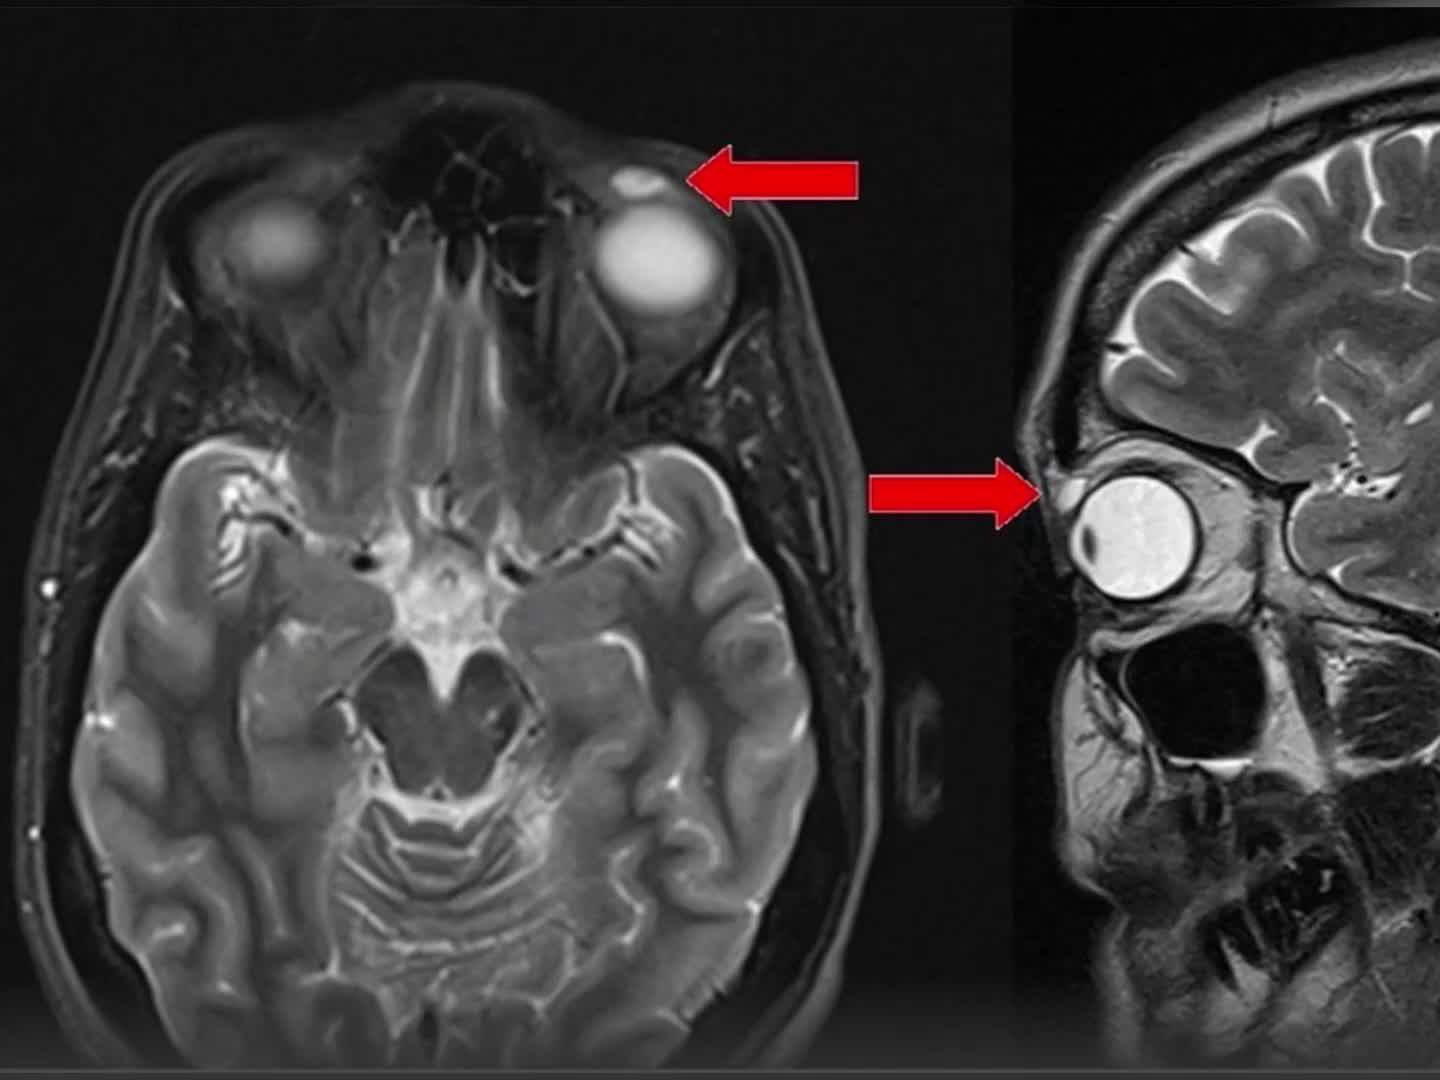

Ärzte haben bei einer Frau aus Großbritannien eine uralte Kontaktlinse im oberen Augenlid entdeckt. 28 Jahre lang steckte die Linse dort schon fest! Die Frau erinnert sich: Als 14-Jährige bekam sie einen Ball an den Kopf, doch dass die Kontaktlinse weiterhin in ihrem Körper war, war ihr nicht bewusst.